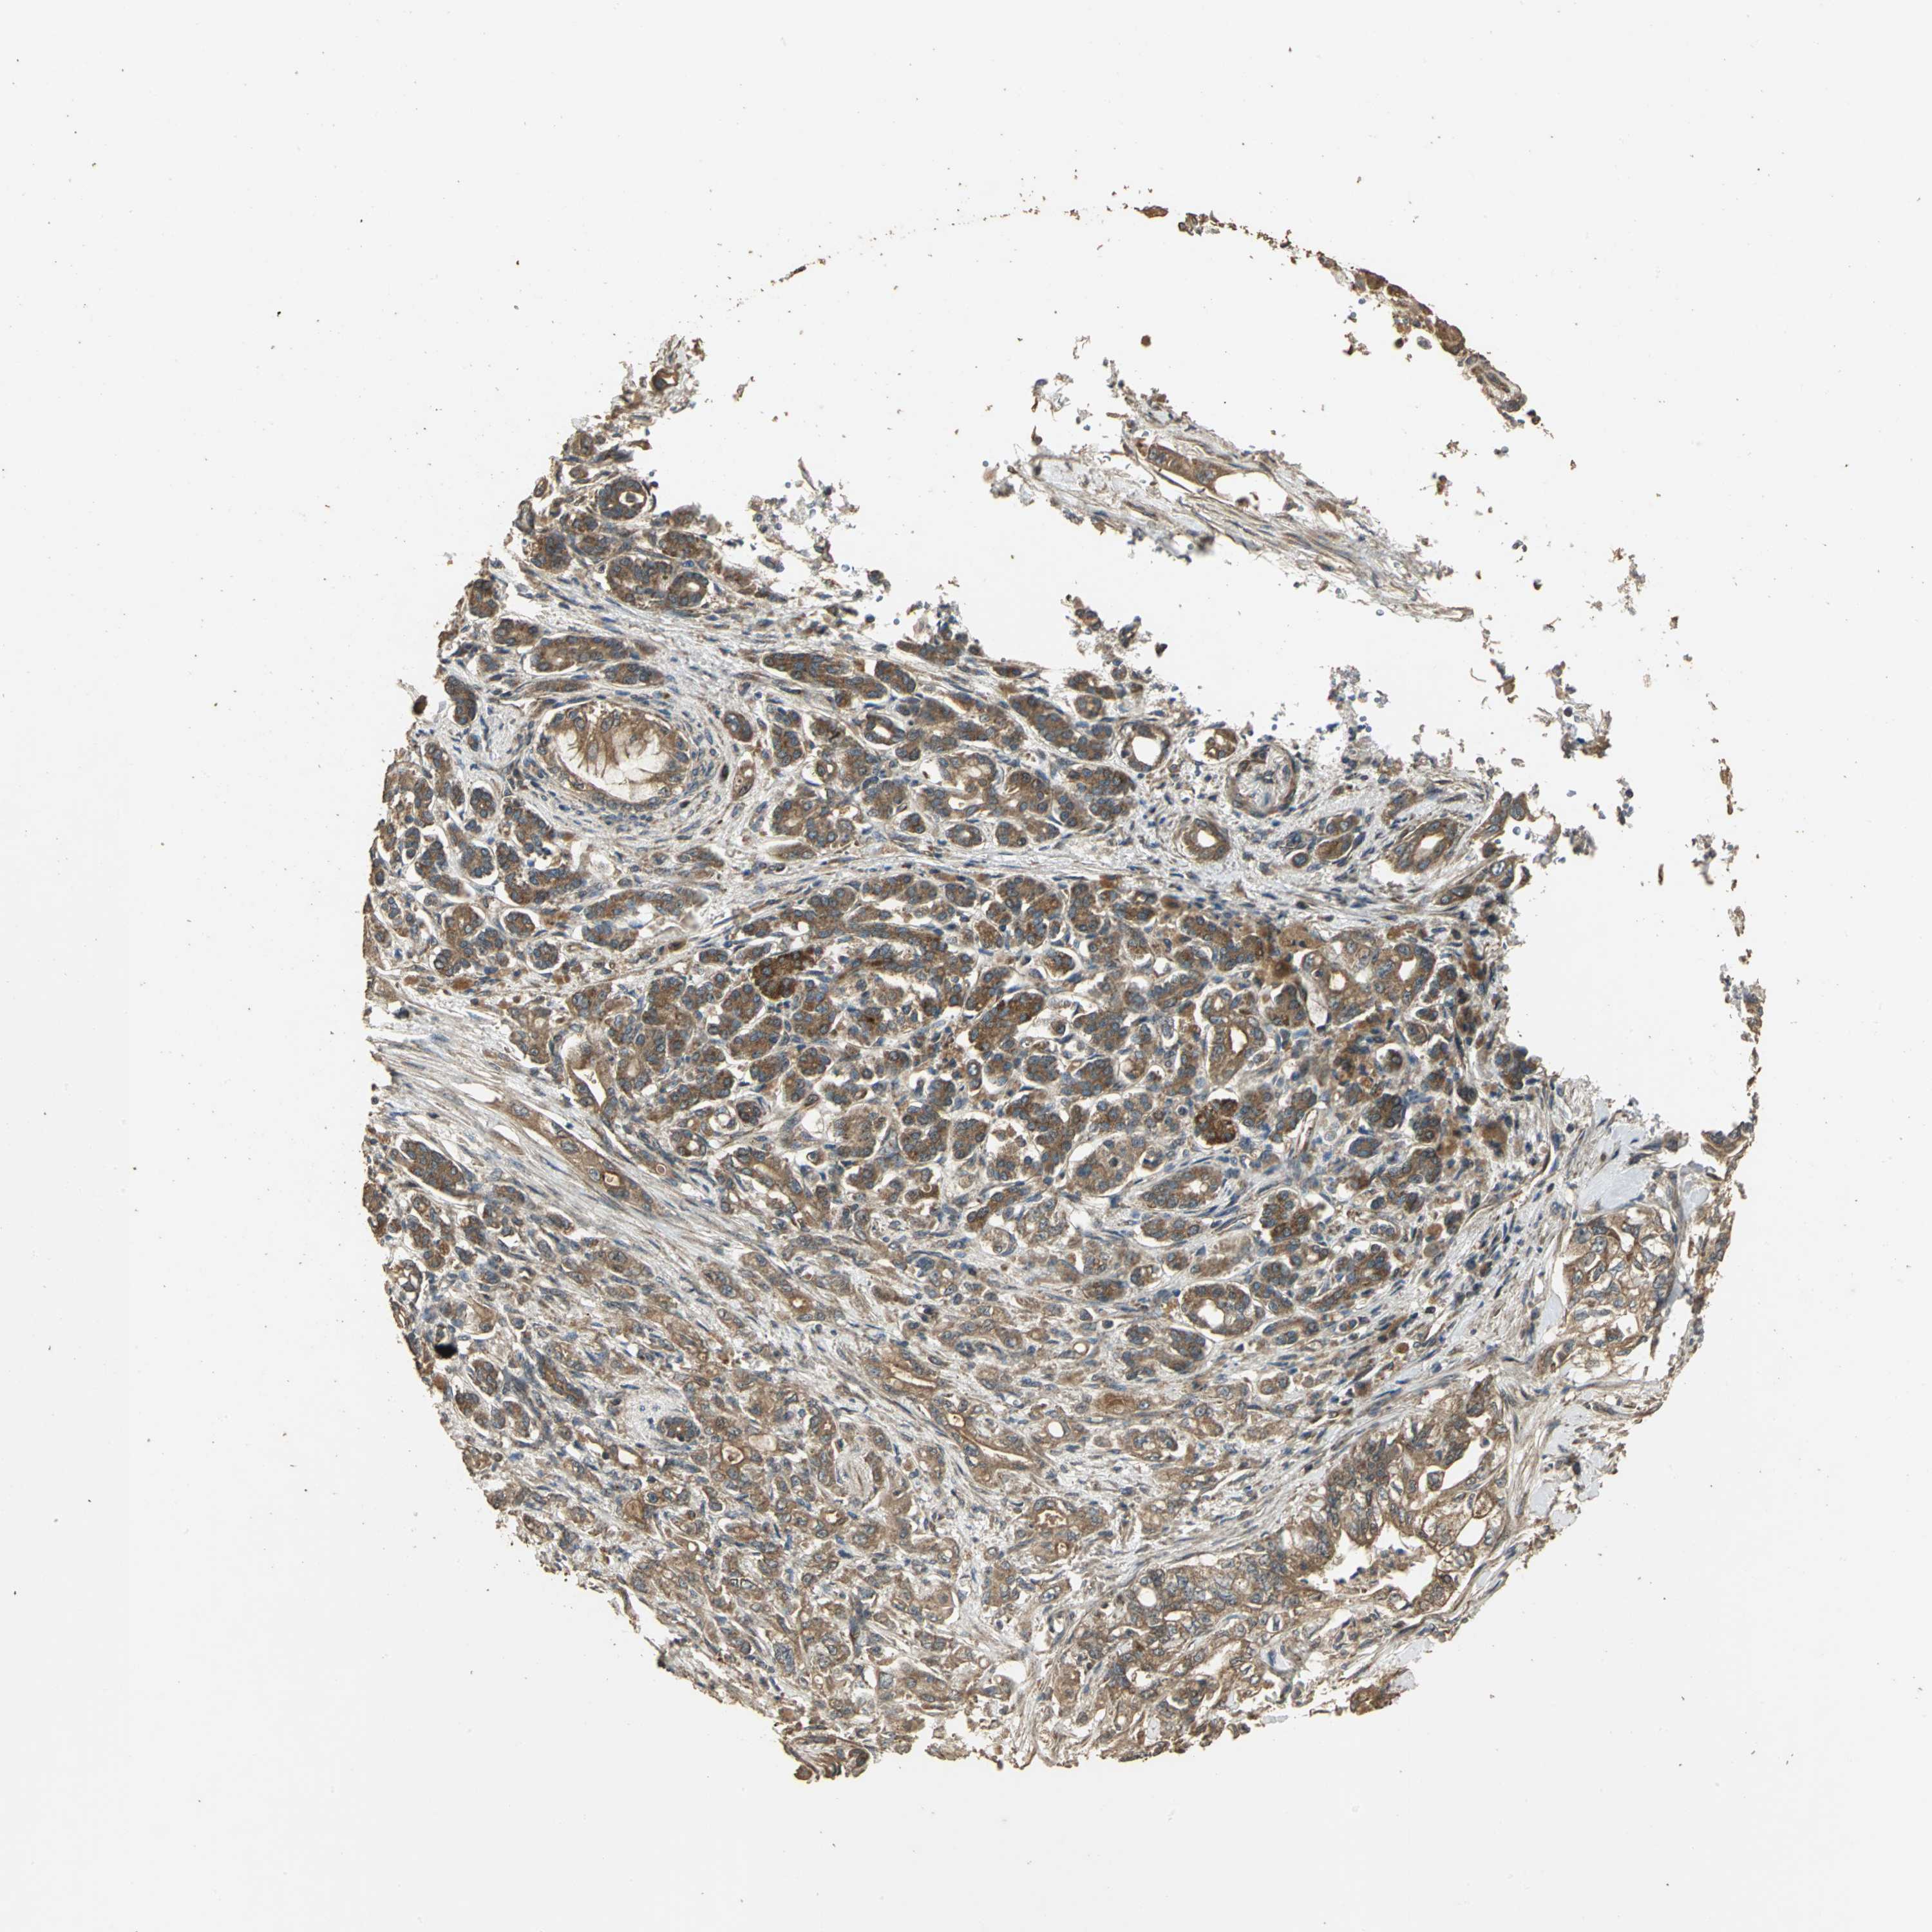

PANCREATIC CANCER - Protein expressioni

A mouse-over function shows sample information and annotation data. Click on an image to view it in a full screen mode. Samples can be filtered based on level of antibody staining by selecting one or several of the following categories: high, medium, low and not detected. The assay and annotation is described here.

Note that samples used for immunohistochemistry by the Human Protein Atlas do not correspond to samples in the TCGA dataset.

Antibody stainingi

Antibody staining in the annotated cell types in the current human tissue is reported as not detected, low, medium, or high, based on conventional immunohistochemistry profiling in selected tissues. This score is based on the combination of the staining intensity and fraction of stained cells.

Each image is clickable and will lead to virtual microscopy that enables deeper exploration of all samples and also displays staining intensity scores, fraction scores and subcellular localization as well as patient and tissue information for each sample.

Antibody HPA005539

Staining

High

Medium

Low

Not detected

Intensity

Strong

Moderate

Weak

Negative

Quantity

>75%

75%-25%

<25%

None

Location

Nuclear

Cytoplasmic/membranous

Cytoplasmic/membranous,nuclear

Adenocarcinoma, NOS

Adenocarcinoma, metastatic, NOS